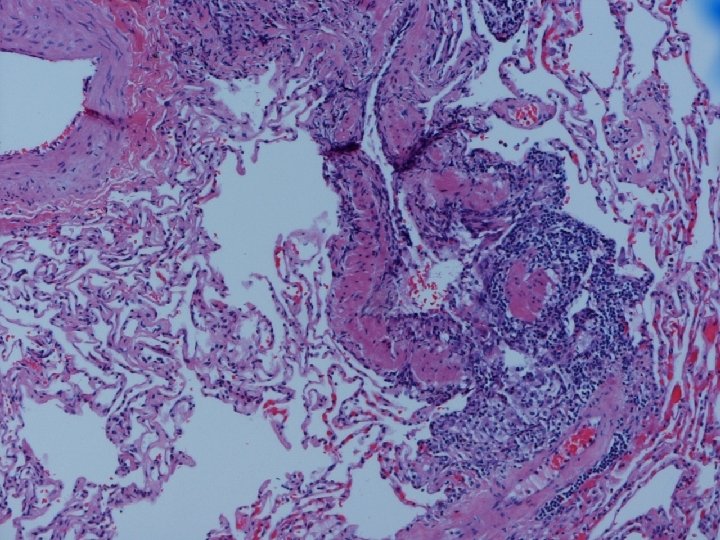

Lung biopsy revealed chronic bronchiolitis/ hypersensitivity pneumonitis (extrinsic allergic alveolitis) with opinion from Mayo Clinic path arriving on 3/30/04. “Hot tub lung due to MAC”. I recommended Prednisone 20 mg. daily, but she had major psychiatric complications for which Seroquel was added and prednisone reduced. X-ray, spirometry, and symptoms resolved. Prednisone tapered and stopped in late May. Recurrence of symptoms and rash in August/September.

Acute HP • Clinical-Abrupt • Lab-ESR, IGG, RA, CRP, LDH, BAL lymphocytosis, restrictive physiology • CXR-micronodular interstitial, but freq. normal-HRCT needed, but not absolute • Histopathology-poorly formed, noncaseating interstitial granulomas, monos, giant cells

Subacute or Intermittent HP • Clinical-gradual cough, dyspnea, fatigue, anorexia, wt. loss, malaise; tachypnea and rales • Lab-BAL lymphocytosis, hypoxemia. Restrictive or mixed spiro, decreased DLCO • CXR-nml, micronodular, reticular. HRCT micronodules, ground glass, emphysema, fibrosis • Histopathology- noncaseating granulomas, bronchiolitis with or w/o organizing pneumonia

Chronic Progressive HP • Clinical-insidious cough, dyspnea, fatigue, weight loss, clubbing • Lab-not very helpful-BAL lymphocytosis but not crisp; restrictive, but usually mixed. DL always reduced, and exertional hypoxemia • CXR-may be normal, but usually progressive fibrosis; emphysema often • Histopathology-granulomatous pneumonia, BO with or w/o OP, fibrosis